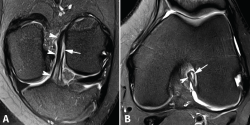

Las secuencias FSE 3D isotrópicas con diferentes nombres comerciales (Space®, Cube®, Vista®, MPV®...) permiten realizar reconstrucciones multiplanares, incluyendo planos oblicuos adaptados al trayecto del LCA(10,11,12,13,14). Estudios recientes muestran que estas secuencias tienen una precisión similar a las secuencias 2D convencionales en la valoración de las lesiones intraarticulares de rodilla. Sin embargo, las imágenes reconstruidas con estas secuencias FSE 3D muestran un mayor grado de distorsión geométrica que dificulta valorar específicamente las lesiones parciales del LCA. La realización de cortes milimétricos oblicuos 2D DP con campo de visión reducido en los planos coronal (siguiendo el trayecto del LCA) y axial (perpendiculares al LCA) permiten obtener imágenes de alta resolución espacial que facilitan una valoración más fiable de las lesiones parciales del LCA(15)(Figura 3).

Figura 3. Anatomía normal del ligamento cruzado anterior (LCA) en cortes oblicuos de resonancia magnética (RM). A: corte oblicuo coronal de RM potenciado en densidad protónica (DP) con supresión grasa adaptado al trayecto del LCA que muestra la anatomía bifascicular normal; B: corte oblicuo axial de RM potenciado en DP con supresión grasa perpendicular al trayecto del LCA que permite valorar el estado de ambos fascículos. AM: fascículo anteromedial; PL: fascículo posterolateral.

Los hallazgos de RM en las roturas parciales del LCA consisten en un aumento de la señal intrasustancial, defectos focales, distorsión y atenuación de fibras o una orientación anormal del ligamento(1,16)(Figuras 4 y 5). El diagnóstico es más sencillo en fase aguda, por la presencia de signos secundarios con edema y derrame articular. La principal dificultad diagnóstica con RM en la fase aguda consiste en diferenciar roturas parciales de alto grado de completas(1,16).